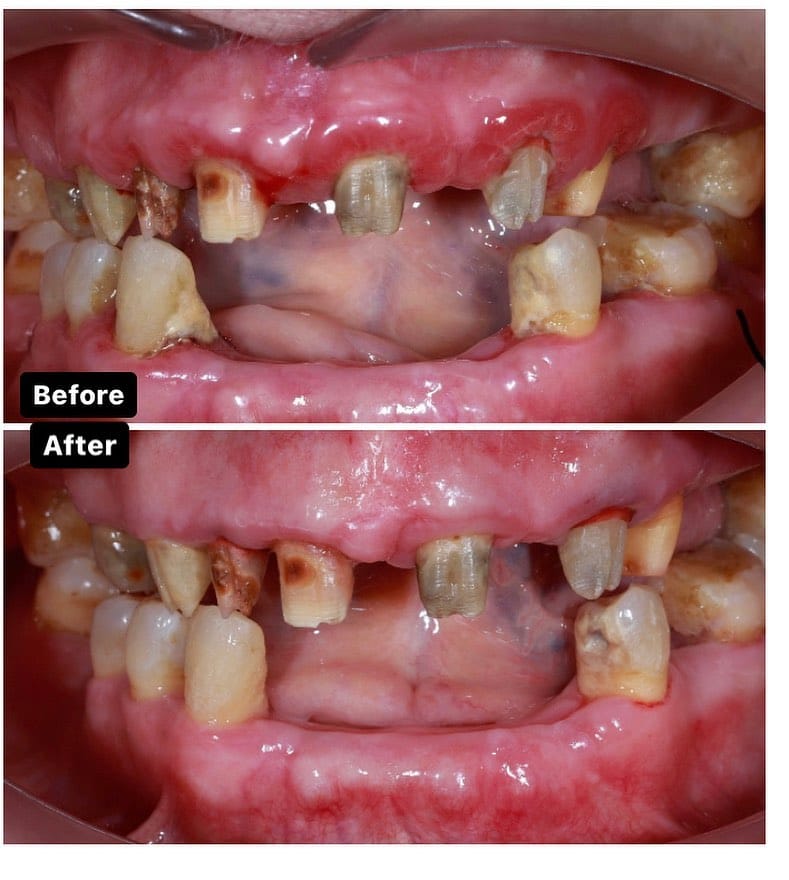

Əvvəl-Sonra

Pasiyentlərimizin nəticələri

Diş ətinin iltihabı

Diş ətində olan qızartı, şişkinlik və qanama kimi əlamətləri olan diş əti xəstəlikləri müalicə olunmalı və sonra qapaq ilə implant edilməlidi